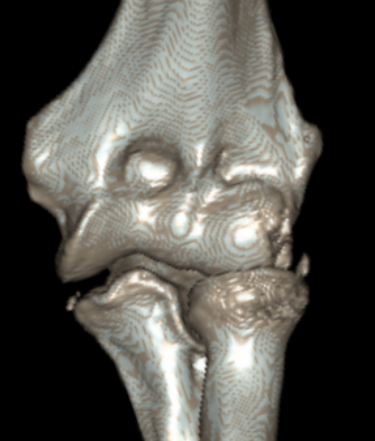

Multiple elbow loose bodies

lblblb